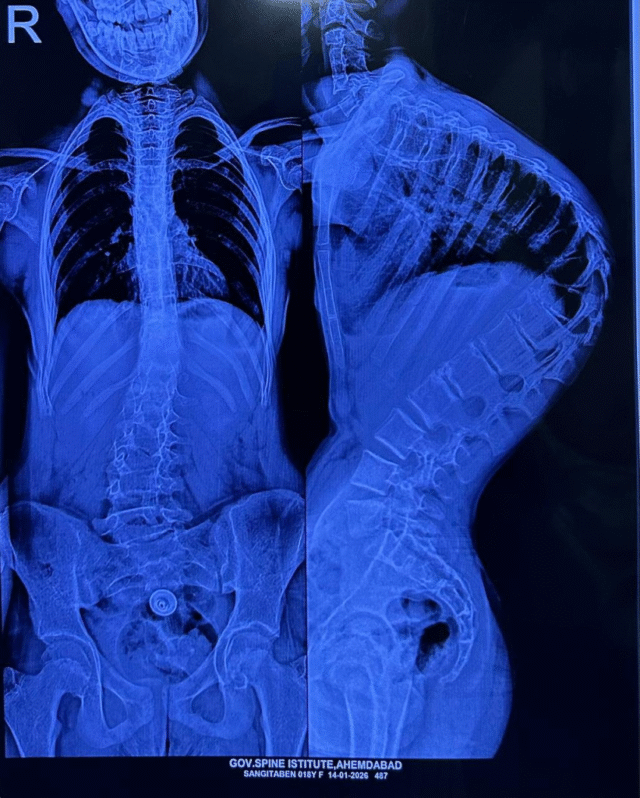

સિવિલ મેડિસિન, અમદાવાદ ખાતે આવેલી સરકારી સ્પાઇન ઇન્સ્ટિટ્યૂટ ફરી એકવાર તબીબી સંશોધન અને માનવતાવાદી સેવાના કેન્દ્ર તરીકે ઉભરી આવી છે. ગુજરાત સરકારના આરોગ્ય અને પરિવાર કલ્યાણ વિભાગના સહયોગથી આયોજિત ‘ઇન્ડો-અમેરિકન સ્પાઇન સર્જરી કેમ્પ’ અંતર્ગત કરોડરજ્જુની ખૂબ જ જટિલ વિકૃતિથી પીડાતા 7 બાળકોના સફળ ઓપરેશન કરવામાં આવ્યા હતા. વૈશ્વિક આંકડાઓ અનુસાર, આ શિબિર કિફોસિસ અને સ્કોલિયોસિસ જેવી વિકૃતિઓ સામે નવી આશા લઈને આવી છે, જે દર 1000 બાળકોમાંથી 1 બાળકમાં જોવા મળે છે.

‘કાયફોસ્કોલિયોસિસ’ એક ગંભીર રોગ છે જેમાં બાળકની કરોડરજ્જુ સાપની જેમ વાંકા વળી જાય છે, તેની સારવાર સામાન્ય મધ્યમ વર્ગ માટે સ્વપ્ન સમાન છે. પરંતુ, ઈન્ડો-અમેરિકન સર્જરી કેમ્પ દ્વારા આ સપનું સાકાર થયું છે.

સર્જરીની જટિલતા અંગે ઈન્ડો-અમેરિકન સર્જરી કેમ્પના ડોકટરોનું કહેવું છે કે આ ખૂબ જ જટિલ સર્જરી છે. આ શસ્ત્રક્રિયા, જે સરેરાશ 4 થી 5 કલાક ચાલે છે, તેમાં કરોડરજ્જુને સીધી કરતી વખતે ખૂબ જ નાજુક ચેતા અને રક્તવાહિનીઓ વચ્ચે કામ કરવાનો સમાવેશ થાય છે.

સર્જરી દરમિયાન મુખ્ય પડકાર સતત ‘ન્યુરો-મોનિટરિંગ’ છે. જો કોઈ પણ પગલું ખોટું થઈ જાય, તો દર્દીનું મૃત્યુ થઈ શકે છે અથવા મોટી રક્ત વાહિનીમાં ઈજાને કારણે જીવનભર લકવો થઈ શકે છે. આ જોખમને દૂર કરવા માટે, અમેરિકન ન્યુરો-મોનિટરિંગ ટીમ અને એનેસ્થેસિયા નિષ્ણાતોએ તકનીકી સહાય પણ પ્રદાન કરી.